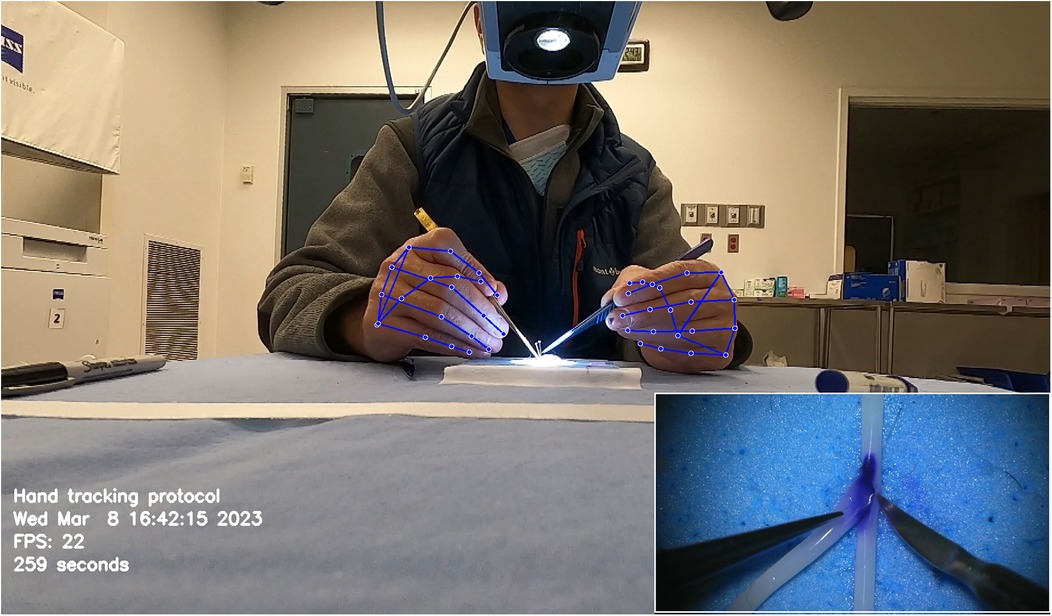

Similarly, Gonzalez-Romo et al. (11) reported a sensor-free hand-tracking method using a motion-detector program created with the Python programming language (Python Software Foundation, https://www.python.org/) and a machine learning system developed by Google (Mediapipe) (https://ai.google.dev/edge/mediapipe/solutions/guide). The aim was to analyze hand movements during microanastomosis training. They also demonstrated the effectiveness of ML in assessing hand movement metrics without any physical sensors (Figure 7) (11).

Figure 7. Hand tracking using a machine learning system developed by Google (Mediapipe) (https://ai.google.dev/edge/mediapipe/solutions/guide). The neural network automatically detects hands without requiring preliminary registration. The hand-tracking process starts with activating a palm detector, followed by a landmark detector once the hands are located in the image. At the beginning of the hand-tracking session, the operator is asked to display both hands to the camera to ensure swift activation of the model. The effectiveness of hand detection is validated by displaying real-time tracking data during the simulation. This photograph was taken during microvascular anastomosis training at the Loyal and Edith Davis Neurosurgical Research Laboratory, Barrow Neurological Institute, in Phoenix, Arizona. Used with permission from Barrow Neurological Institute, Phoenix, Arizona.

Similar methods of hand pose estimation have been used in neurosurgical procedures such as microanastomosis. Gonzalez-Romo et al. published a study that used 21 hand landmarks in conjunction with ML to identify gross and fine movements during microanastomosis procedures for evaluating surgeons' performance (Figure 7) (11). The Python programming language was used to develop a motion detector incorporating Google Mediapipe (https://ai.google.dev/edge/mediapipe/solutions/guide). This motion detector was able to analyze videos of anastomosis procedures to track the motion of hands in a physical sensor-free manner.